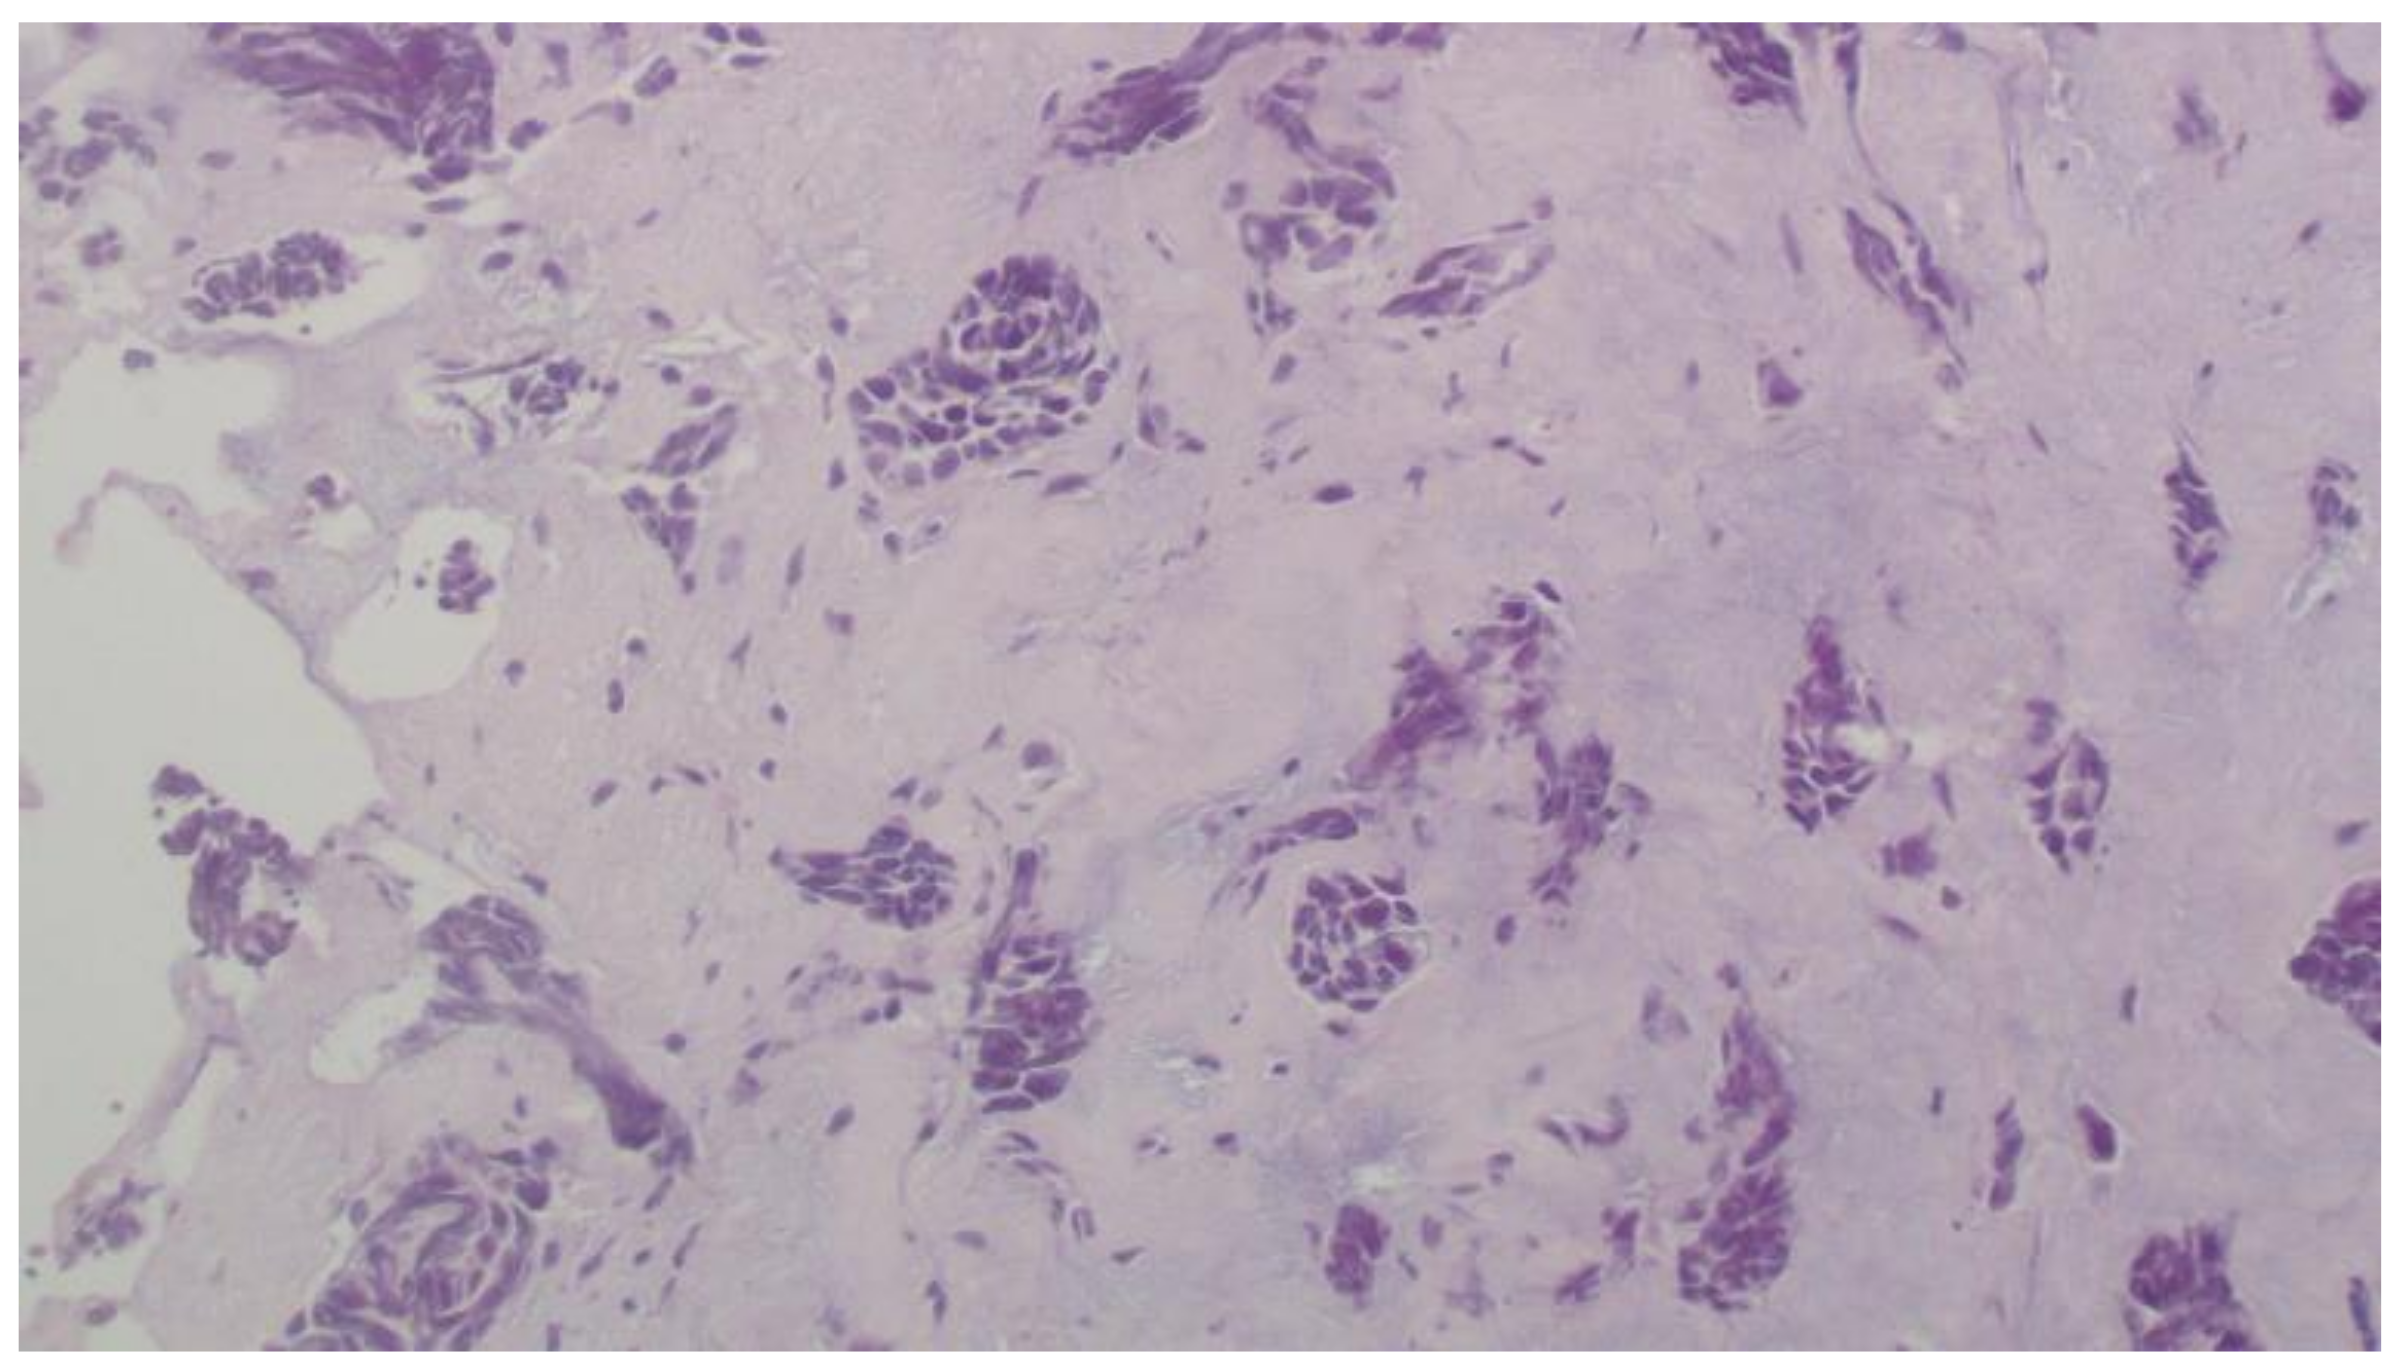

2. Case Report